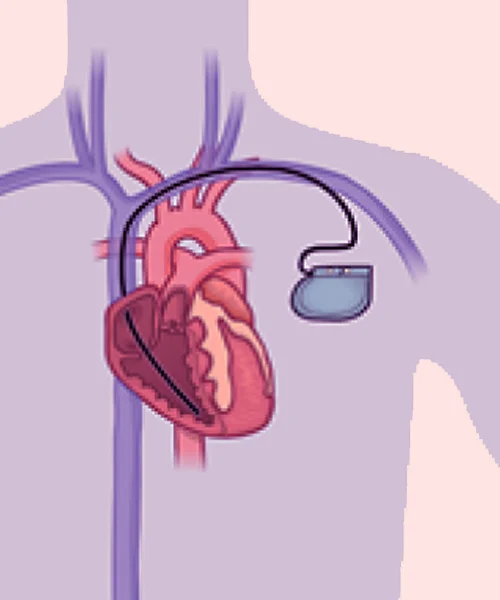

He holds prestigious qualifications including MBBS, MD in General Medicine, and DM in Cardiology, making him a highly skilled expert in interventional cardiology. Dr. Yogesh Nagendra has extensive expertise in procedures such as angiography, angioplasty, pacemaker implantation, Balloon Mitral Valvotomy (BMV), ECHO, and TMT, ensuring accurate diagnosis and effective treatment for every patient.